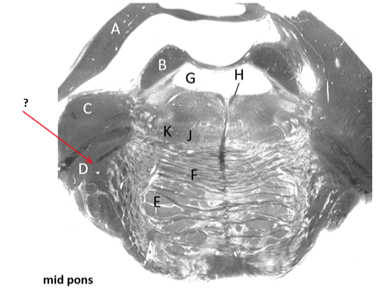

Name this and state its function.

What does it connect?

Middle cerebellar peduncle.